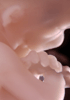

Carnegie Stage 23 (56 post-ovulatory days)

Most embryos at stage 23 are approximately 56-57 postovulatory days old and measure 23-32 mm in length. Distinguishing criteria for this stage include fusion of the eyelids at the medial and lateral margins, clear distinction of the subdivisions of the upper and lower limbs, the forearms appear at or above the level of the shoulders, the superficial vascular plexus of the head is very close to the vertex, and the external genitalia are well developed but not always sufficiently to distinguish the embryo's sex.

(NOTE: These specimens are late stage 23.)